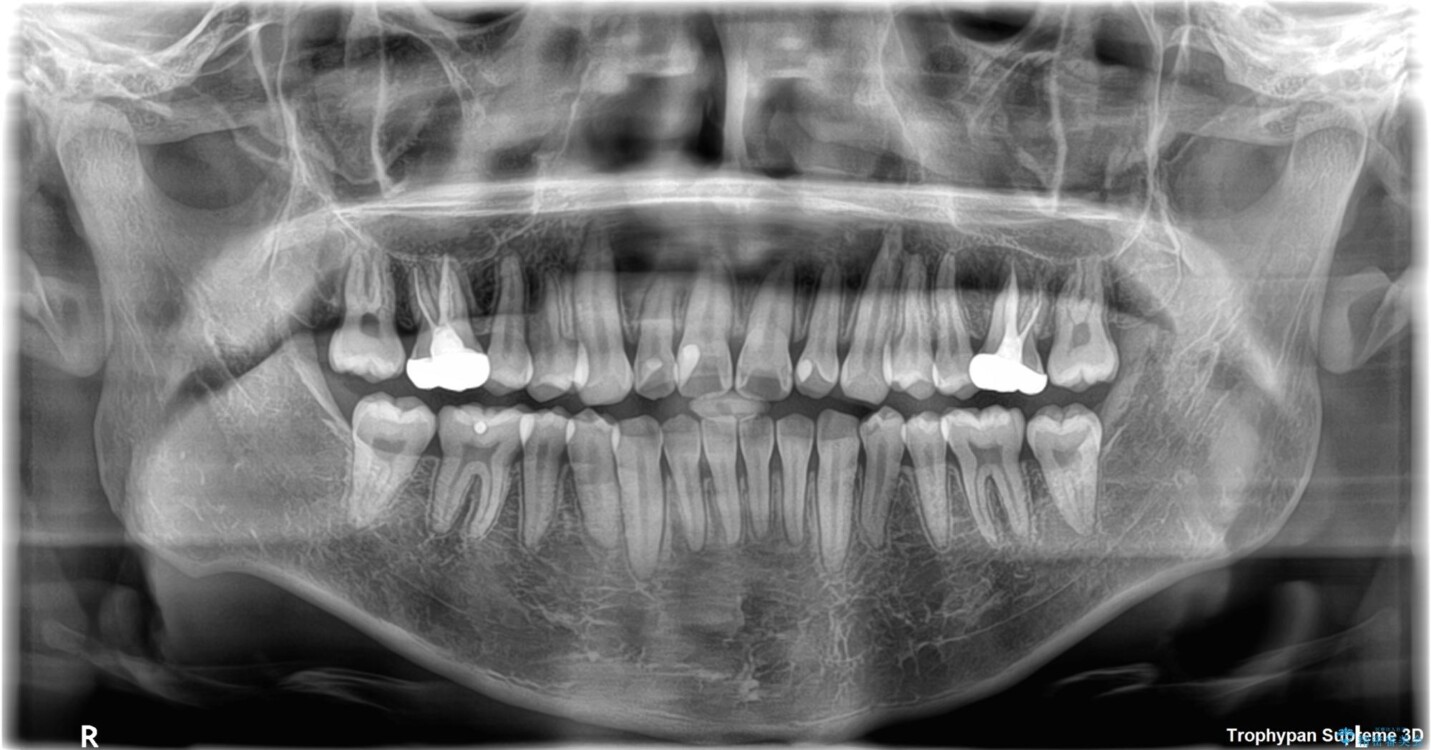

初診時の状態

・上下ともに歯がきれいに並びきらず、がたつきが見られました。

・上下の前歯の中心(正中)がずれています。

・特に上顎の幅が狭いため、下顎の歯列も内側に入り込み、歯が並ぶスペースが不足していました。

このような歯列の狭さに起因するデコボコを改善するために、**MARPE(骨に固定する上顎急速拡大装置)**を使用して、上顎の横幅を拡大し、これにより歯が並ぶためのスペースを確保し、メタルブラケットを用いて歯列を整えていく計画としました。

• 1年でここまで変わる!歯列のがたつきと正中のズレを改善した矯正治療(メタルブラケット×MARPE) 治療前画像